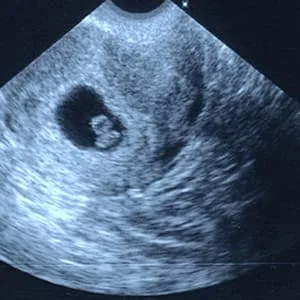

سونوگرافی در هفتمین هفته بارداری

اندازه جنین: در سونوگرافی هفته هفتم طول رویان یا جنین از سر تا نشیمنگاه، ۵ تا ۸ میلیمتر است.

و ضربان قلب در این هفته بهطور حتم قابلمشاهده است.

فاصله بین دهانه رحم تا رحم طول سرویکس میباشد که اندازه آن ان باید بیشتر از ۳ سانت یا بیشتر از ۳۰ میلیمتر باشد و دهانه رحم کاملاً بسته است.